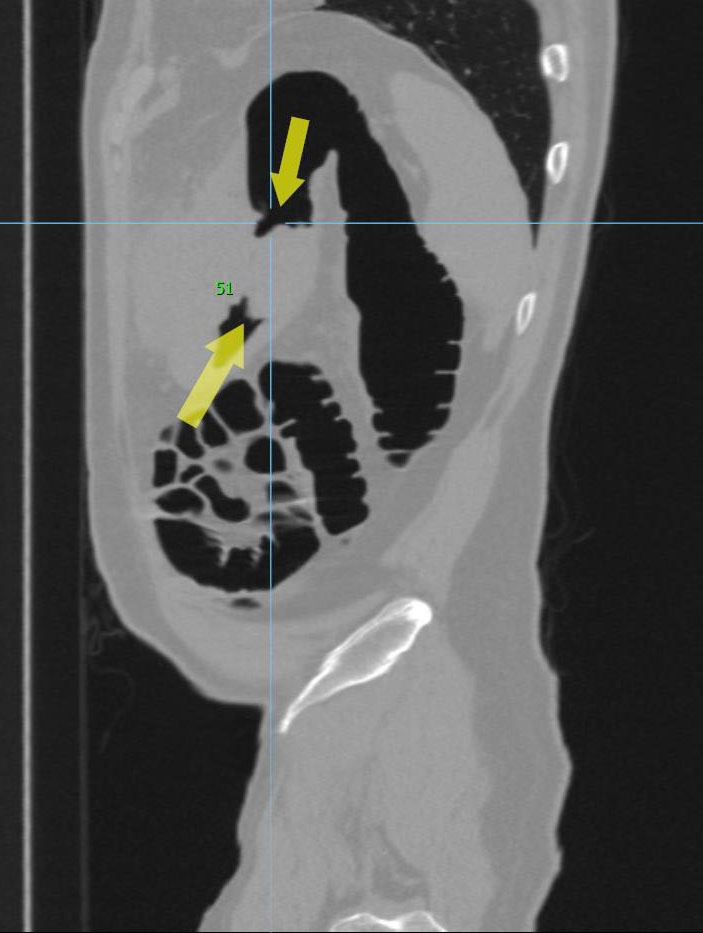

Циркулярный рак тонкой (подвздошной кишки)

Необходимо отметить, что данная патология довольно редко встречается, как правило выявляется на операционном столе у пациентов с тонкокишечной непроходимостью. На данном примере демонстрируем, что дефект кишки был диагностирован на основании 3D реконструкции, а затем уже целенаправленно подтвержден сканограммами с протяженностью процесса и степенью сужения кишечной трубки. Сыграла свою роль сопутствующая патология, которая имела место быть, а именно слабость Баугиниевой заслонки, за счёт чего тонкий кишечник полностью заполнился газом, хотя целью исследования было исключить патологию толстого кишечника.

Просвет тонкой кишки до и после дефекта в 3D-эндоскопе